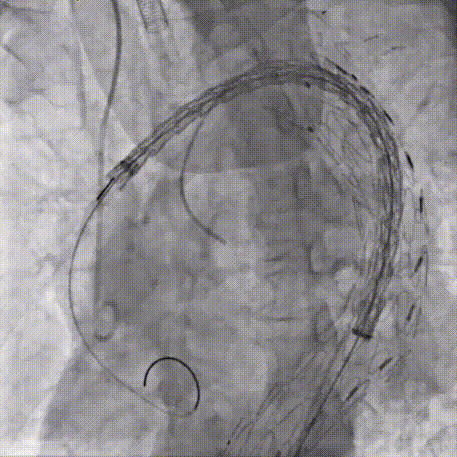

CADS第一步释放,支架从近段向远端打开,释放至50%直径,造影确认调整支架近端位置,精准定位于INA远端。

gore医疗怎么样「胸有乾坤」可调可控 从容不迫——GORE® TAG® 可主动调控胸主动脉覆膜支架治疗巨大胸主动脉瘤病例报道_https://www.jmylbn.com_新闻资讯_第25张

gore医疗怎么样「胸有乾坤」可调可控 从容不迫——GORE® TAG® 可主动调控胸主动脉覆膜支架治疗巨大胸主动脉瘤病例报道_https://www.jmylbn.com_新闻资讯_第26张

CADS第二步释放,支架从远端向近端打开,释放至全直径;随后可以选择性调整近端成角,优化小弯侧贴壁。